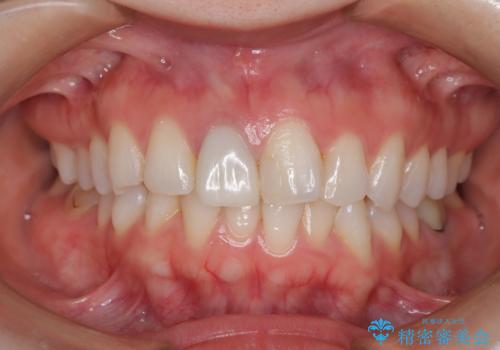

後戻り治療 クロスバイトをマウスピース矯正

- 子供のころに矯正治療をされていたが、後戻りをしてしまったという20代女性の患者様です。上顎左右の2番が、咬合時に下顎の歯よりも内側に入っているクロスバイトという状態でした。奥歯の咬合関係は変えずに、マウスピース矯正にて前歯の並びを綺麗なアーチに仕上げました。再度後戻りしてしまうリスクを軽減させるために、リテーナー(保定装置)をお渡ししています。